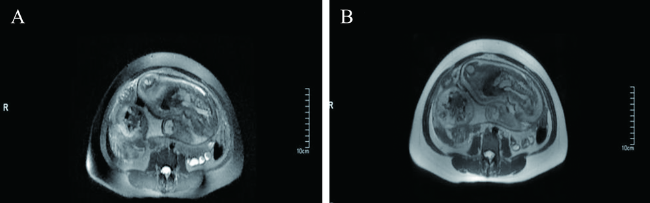

入院血常规:血红蛋白80 g/L,红细胞3.1×1012/L,白细胞9.0×109/L,中性粒细胞0.75,淋巴细胞0.25,血小板552.0×109/L。尿常规:白细胞计数10 909/μl,细菌计数342.97/μl。血超敏CRP 203 mg/L,降钙素原0.0045 μg/L。三维彩超表现:子宫内见一胚型,轮廓不清,胎头颅骨光环已变形,臀位,胎心未闻及,双顶径5.6 cm,头围23.4 cm,胎盘成熟度Ⅱ~Ⅲ级,子宫颈内口上方见胎盘组织,羊水指数几乎为0,子宫后方可见5.0 cm×4.0 cm网格无回声,形态欠清,界限欠清。超声诊断:宫内单死胎,胎龄35+2周,无羊水,胎盘前置状态,孕妇盆腔囊性包块。盆腔MRI表现:子宫壁菲薄,可见胎儿部分肢体向后下方突出于子宫轮廓,邻近子宫后下壁局部肌层信号不连续,周围盆腔内见囊性低T1、高T2信号,胎盘轮廓显示不清,部分达子宫内口,见图1。MRI诊断:不排除子宫破裂,部分前置胎盘。

图1 一例妊娠中晚期胎死宫内、子宫破裂并坏死的MRI检查结果

A:重复时间 899.7 ms,回波时间56.0 ms;B:重复时间 883.4 ms,回波时间55.9 ms